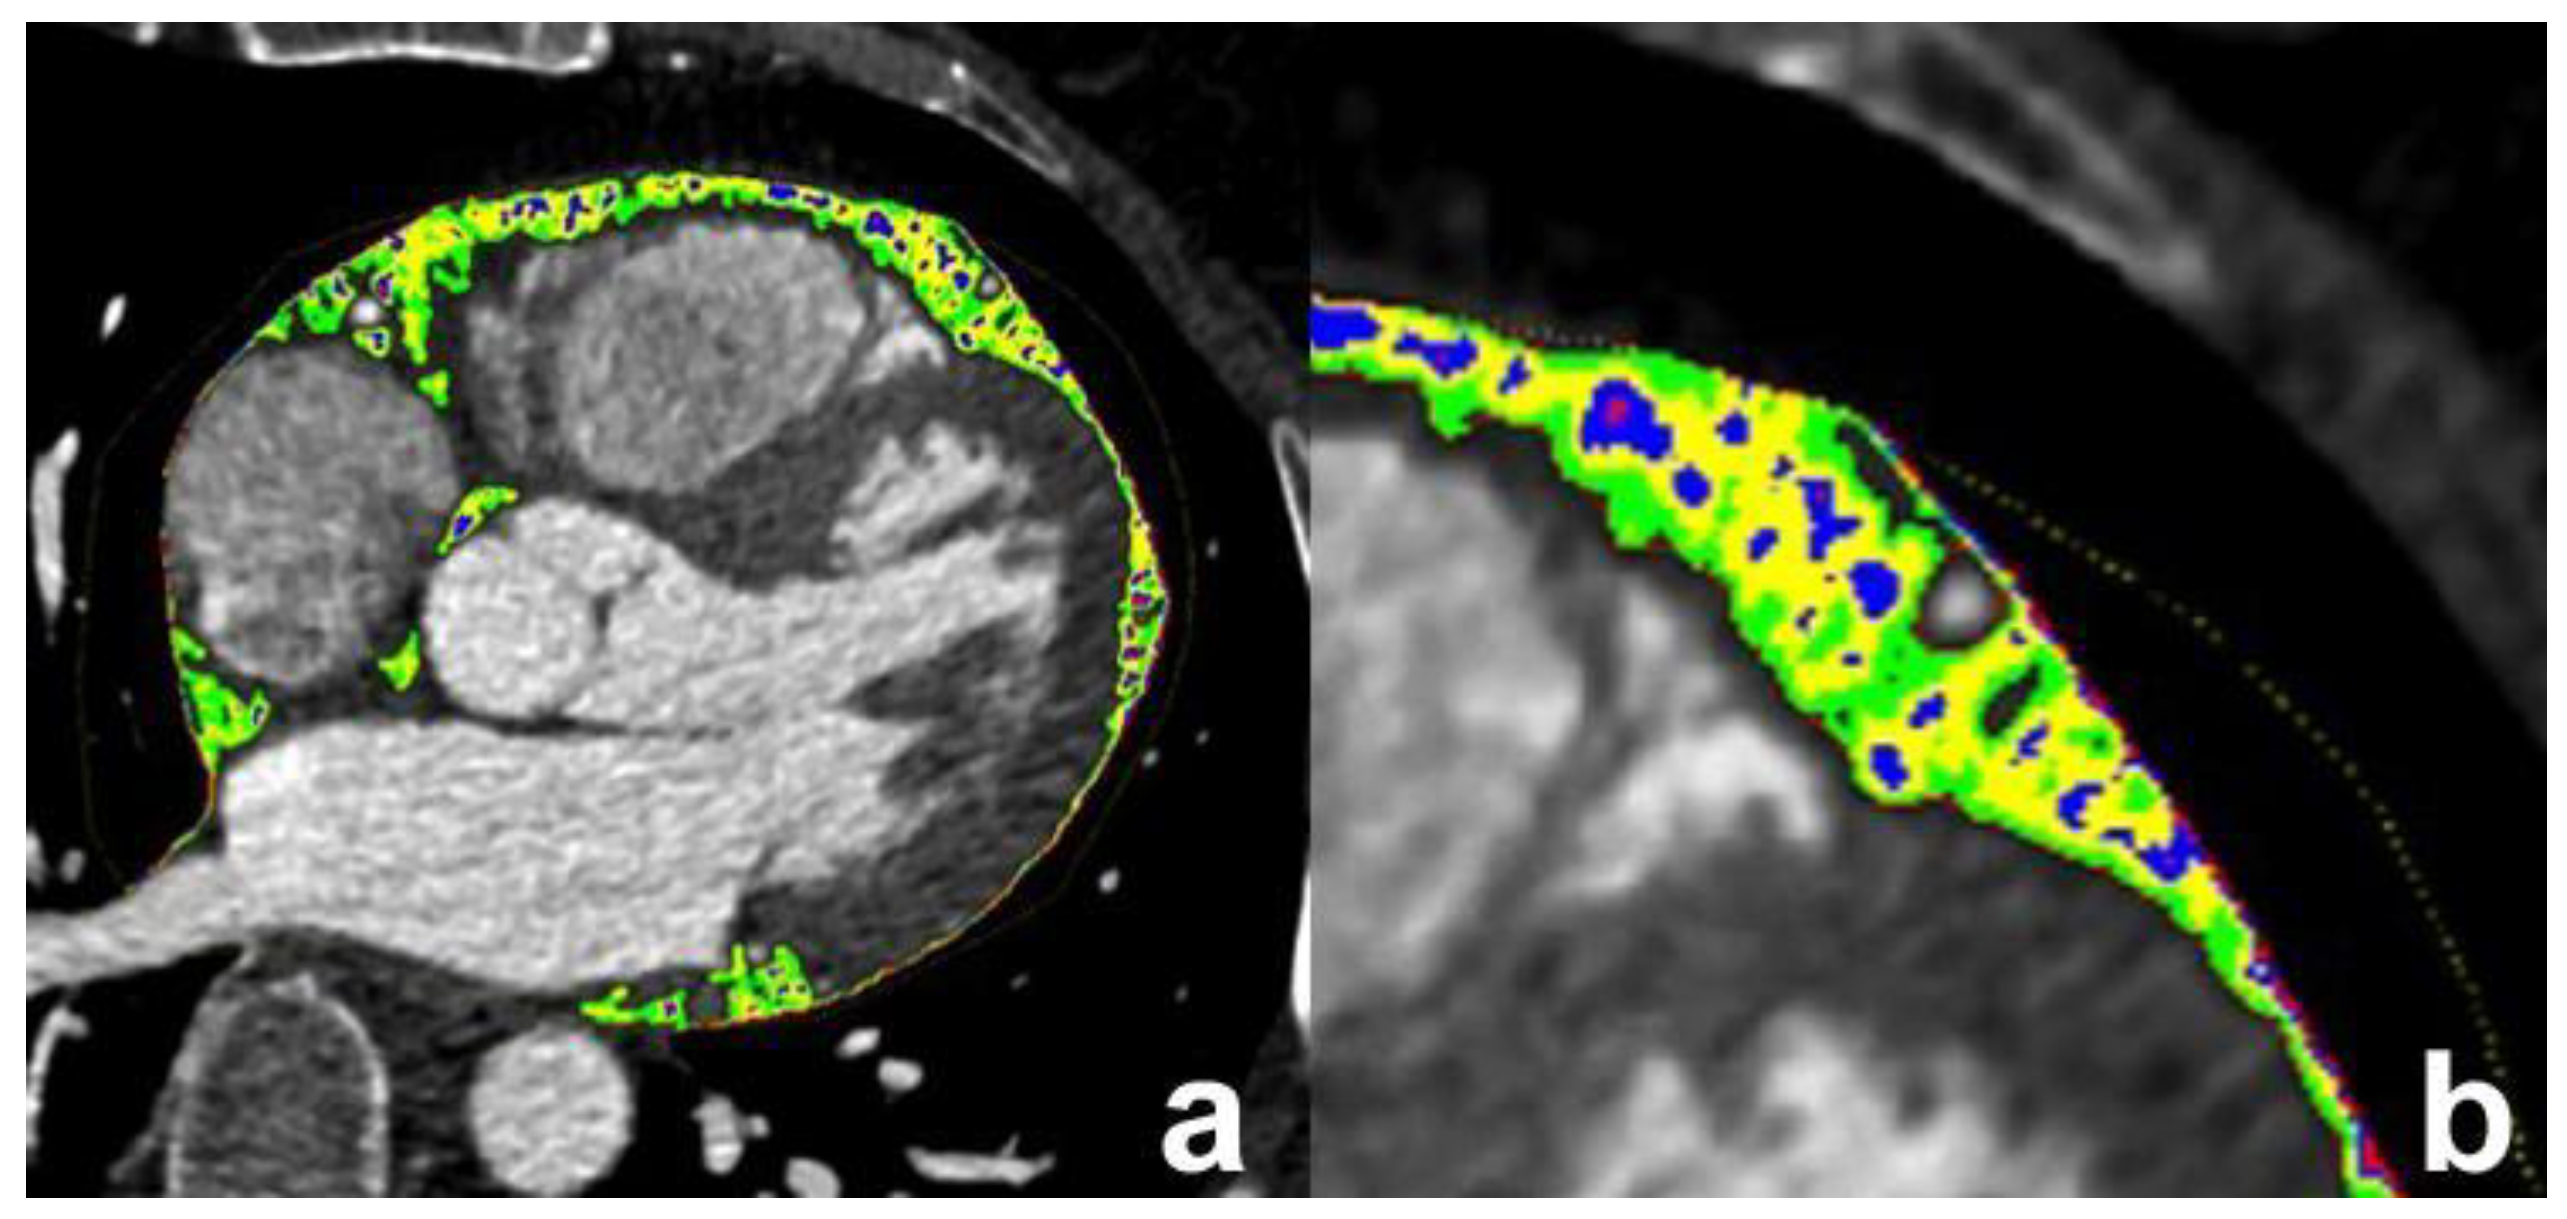

The output provided the overall EAT volume (in cm3) as well as the area/volume for each single image. The voxels representing EAT were used for calculation only when they had HU values within a pre-specified range [16]. The HU range of interest was set between −175 HU and −15 HU, and the quartiles (Q) of attenuation (i.e., Q1, Q2, Q3, Q4) considering the selected interval of density, were computed accordingly [12,13]. In addition, the mean HU value, and the percentages of distribution with respect to the whole EAT volume were calculated. Figure 2 shows an example of segmented fat with the corresponding quartiles, which are represented in different colors and overlapped on the native CCT image.

Figure 2.

Epicardial adipose tissue segmentation (a) and magnification (b): the epicardial adipose tissue quartiles (Q1, Q2, Q3, and Q4) are denoted in red, blue, yellow and green colors, respectively.